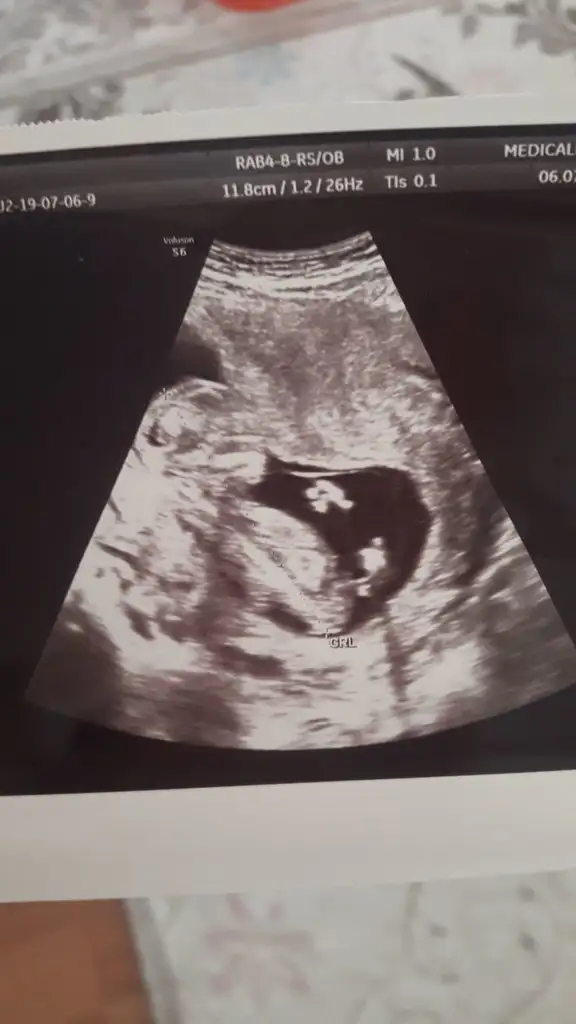

Kizlar bu gecen haftaki usg miz. Cinsiyet icin yorum yapabilir misiniz? 12+4 tu o zaman

Eklentiler

• IMG-20190708-WA0006.webp

18,8 KB · Görüntüleme: 40

• IMG-20190708-WA0008.webp

14,1 KB · Görüntüleme: 45